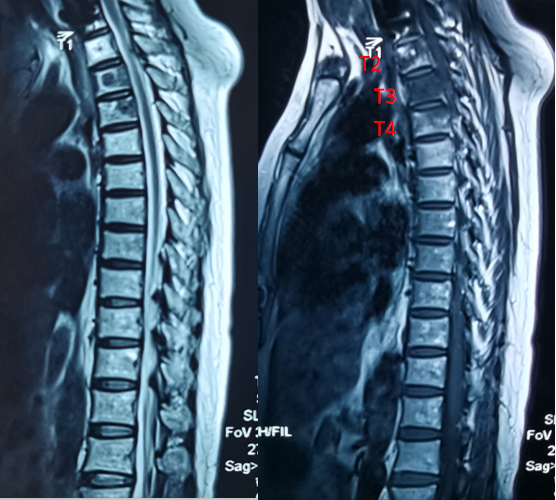

此为戴阿姨术前的MRI图像,标记为转移瘤